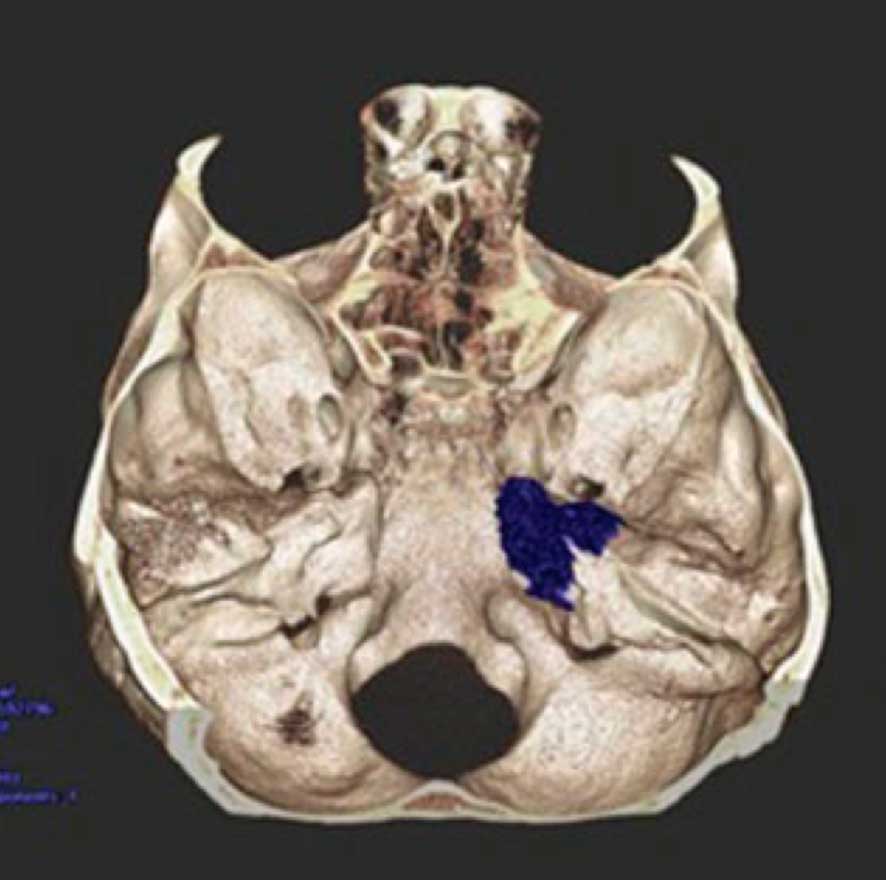

Volumetria e análise de variantes anatômicas da porção anterior do ápice petroso delineado pelo triângulo de Kawase usando tomografia computadoriza

O Apex petroso é um importante corredor cirúrgico para tratar meningeomas e neurinomas da base do crânio. Este estudo foi a tese de mestrado do Dr Juliano Adams Perez, orientada pelo dr Gustavo isolan e foi publicado no Skull Base Journal.